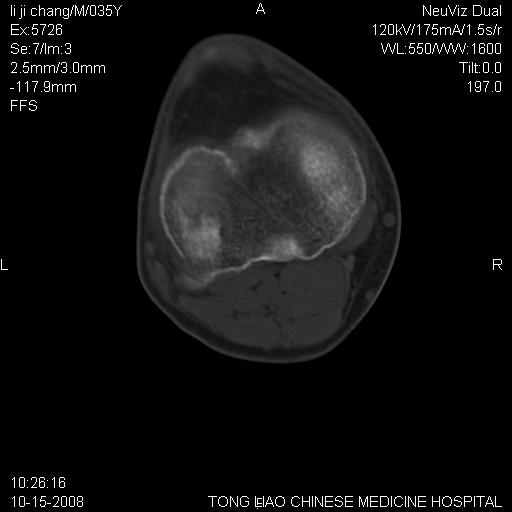

男,35岁,骨科诊断骨性关节炎。继往使用过激素,现股骨头坏死。膝关节病变,请会诊

一元论-----亦考虑为坏死

支持考虑无菌坏死

支持无菌坏死伴退行性骨关节病.

剥脱性骨软骨炎:是一种关节下软骨及软骨下骨缺血性坏死。

支持 无菌性坏死伴退行性骨关节病。

支持无菌坏死伴退行性骨关节病